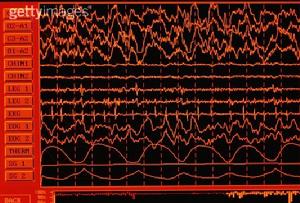

腦電圖【鑑別診斷】應注意與流行性腦脊髓膜炎、乙型腦炎、化膿性腦膜炎和敗血症相鑑別。

6.腦電圖:呈瀰漫性腦病改變,背景波呈廣泛高幅活動,有的有棘波(癲癇樣放電)。